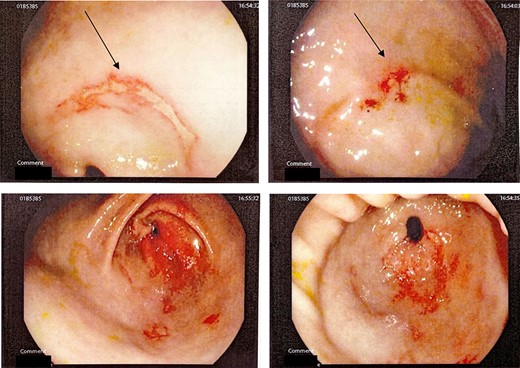

This is a case of a 12-year-old Caucasian female with a background history of autism spectrum disorder presented to the emergency department of a rural hospital in Australia after the ingestion of two NiMH batteries. This is the third presentation of battery ingestion in 2 weeks. She was asymptomatic and did not complain of abdominal pain at the time of review. On examination, she had a soft abdomen with mild epigastric tenderness and guarding. Abdominal radiograph showed the presence of two battery structures projecting to the left of the upper abdominal area overlying L1/2 discs (Fig. 1). To the right of L2, there are two other round devices resembling metallic-type foreign bodies. A gastroscopy was performed 3 hours after her presentation. The gastroscopy revealed extensive superficial erosion to the antral and greater curvature (Fig. 2). Two NiMH batteries were retrieved. However, the other two smaller foreign bodies have passed the jejunum proximally and were unable to be retrieved. She was discharged home on sucralfate, pantoprazole and ColonLYTELY to promote passage of the remaining foreign bodies. Abdominal X-ray was repeated after 1 week, which showed no further foreign objects retained in the patient’s body. She recovered uneventfully with no development of any residual symptoms.

Abdominal X-ray demonstrating four battery-shaped foreign body at the level of L1/L2.